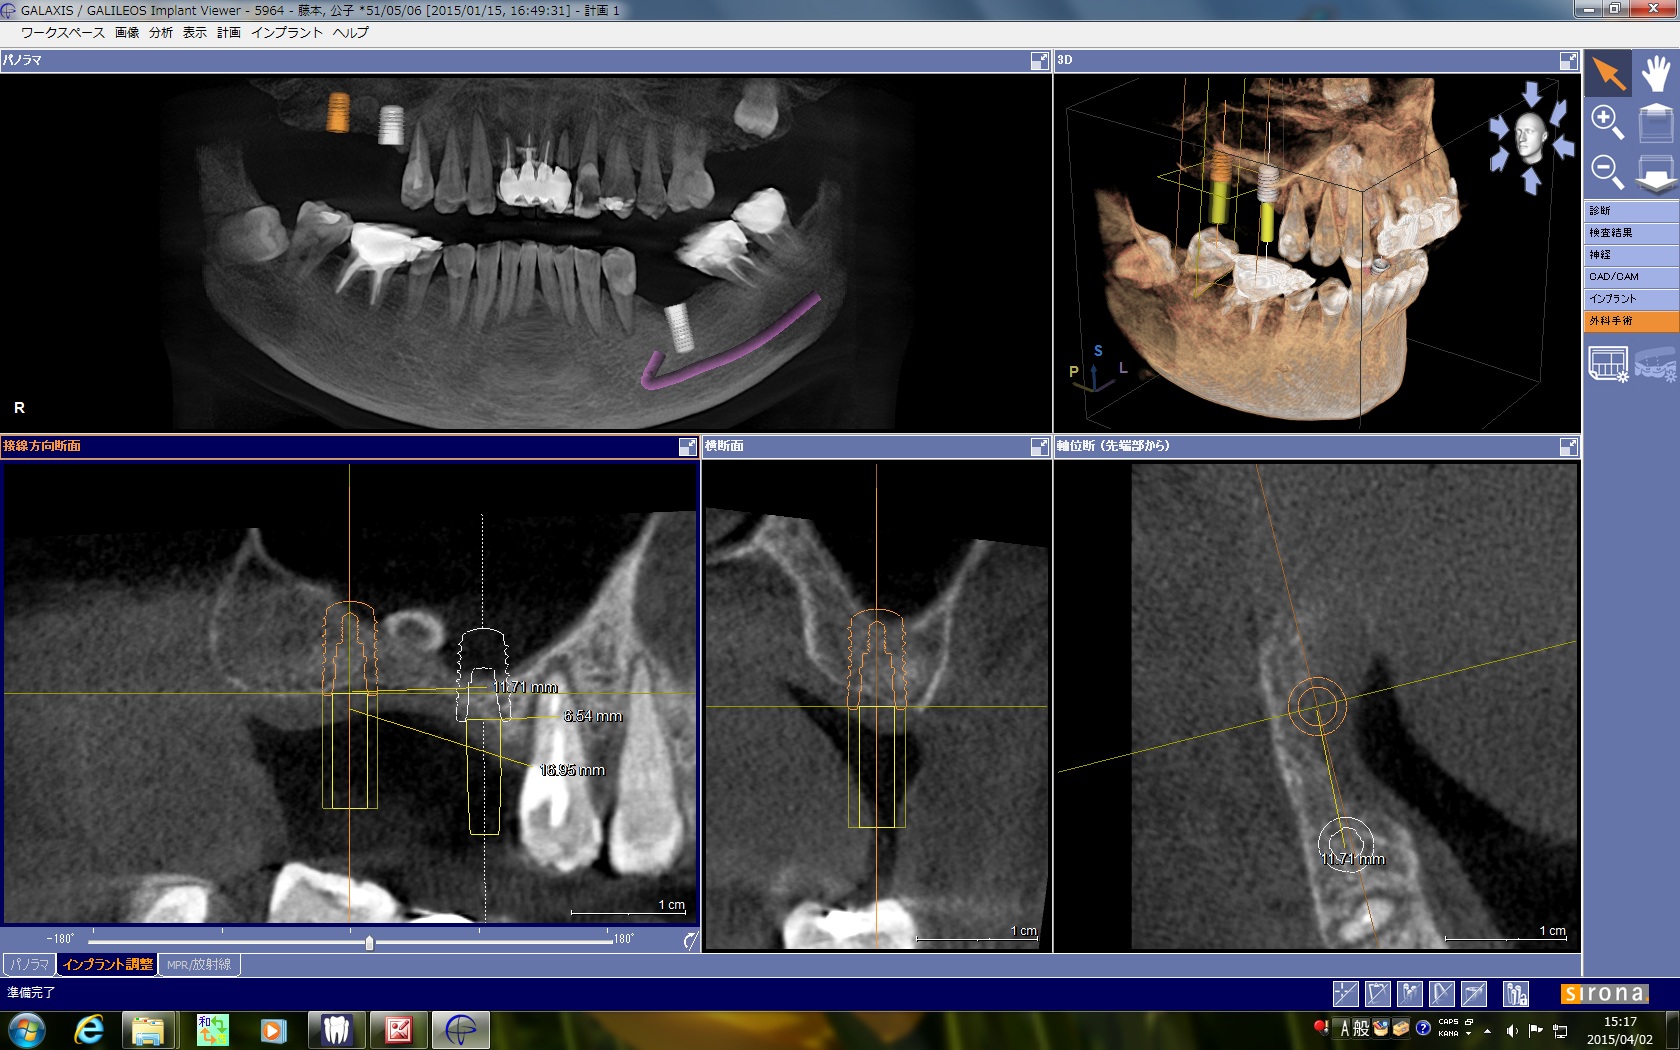

術前のCTで上顎洞の中に骨瘤起が見られました。

骨隆起を避けてソケットリフトでシュナイダー膜を挙上するのですが、あまり骨隆起に近いとうまく粘膜が剥離できない可能性があるので、6番は極力近心部位に、7番は挙上量を少なくするために8mmのショートインプラントを用いました。

術前のCTでは、上顎洞内にまん丸い不透過像が見られます。たぶん骨と思われます。